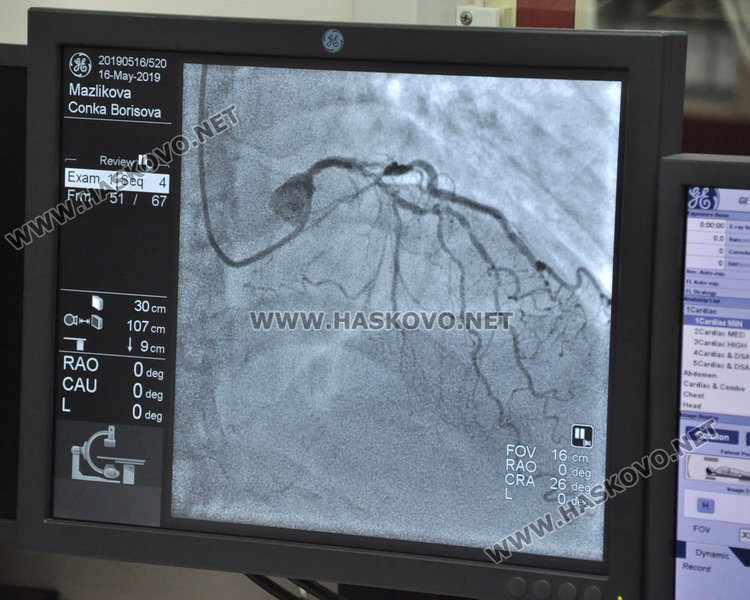

Малко преди обед днес на масата в операционната  в инвазивното звено също има пациент.

Жената е на 69 години. В случая ѝ е направена диагностика, при която се оказва, че няма незасегнат съд на сърцето. Заради това д-р Топалов я изпрати за поставяне на байпас.

Пациентката е имала оплаквания от една година, типични за стенокардна симптоматика – тежест в гърдите, вече и дори когато е в покой, парене, задух, намален физически капацитет. За първи път идва в отделението за обстоен преглед. При диагностиката докторът вижда, че е преживяла един инфаркт, който не е лекуван. Хубавото е, че при нея поне е запазена камерната функция и има предпоставка за успешна операция при поставянето на байпас, разяснява опитният кардиолог. „За радост при тази пациентка е запазена миокардната функция на сърцето, което е предпоставка за добра оперативна реваскуларизация (б.а.-коронарен байпас), след което жената ще може да живее нормален живот.“, смята д-р Топалов.